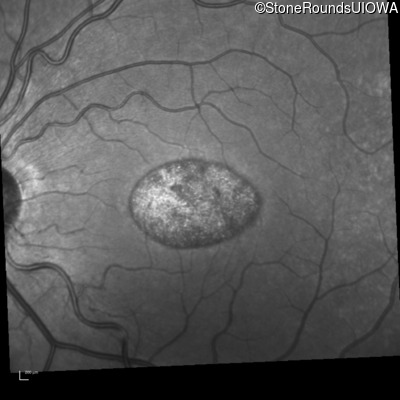

Blue Autofluorescence - Left - 20/100 -2 sc

Exemplar